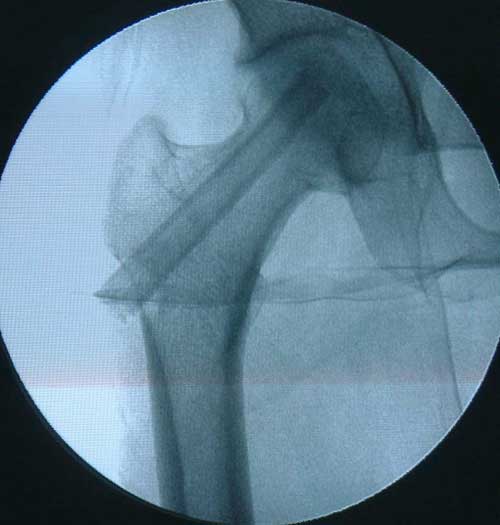

股骨头缺血性坏死MRI显示坏死区                  微创手术方法,采用隧道减压刮除死

BMP植入,异体骨支撑,恢复形态       手术后24个月X线片,关节塌陷未加重,关节功能良好,无疼痛